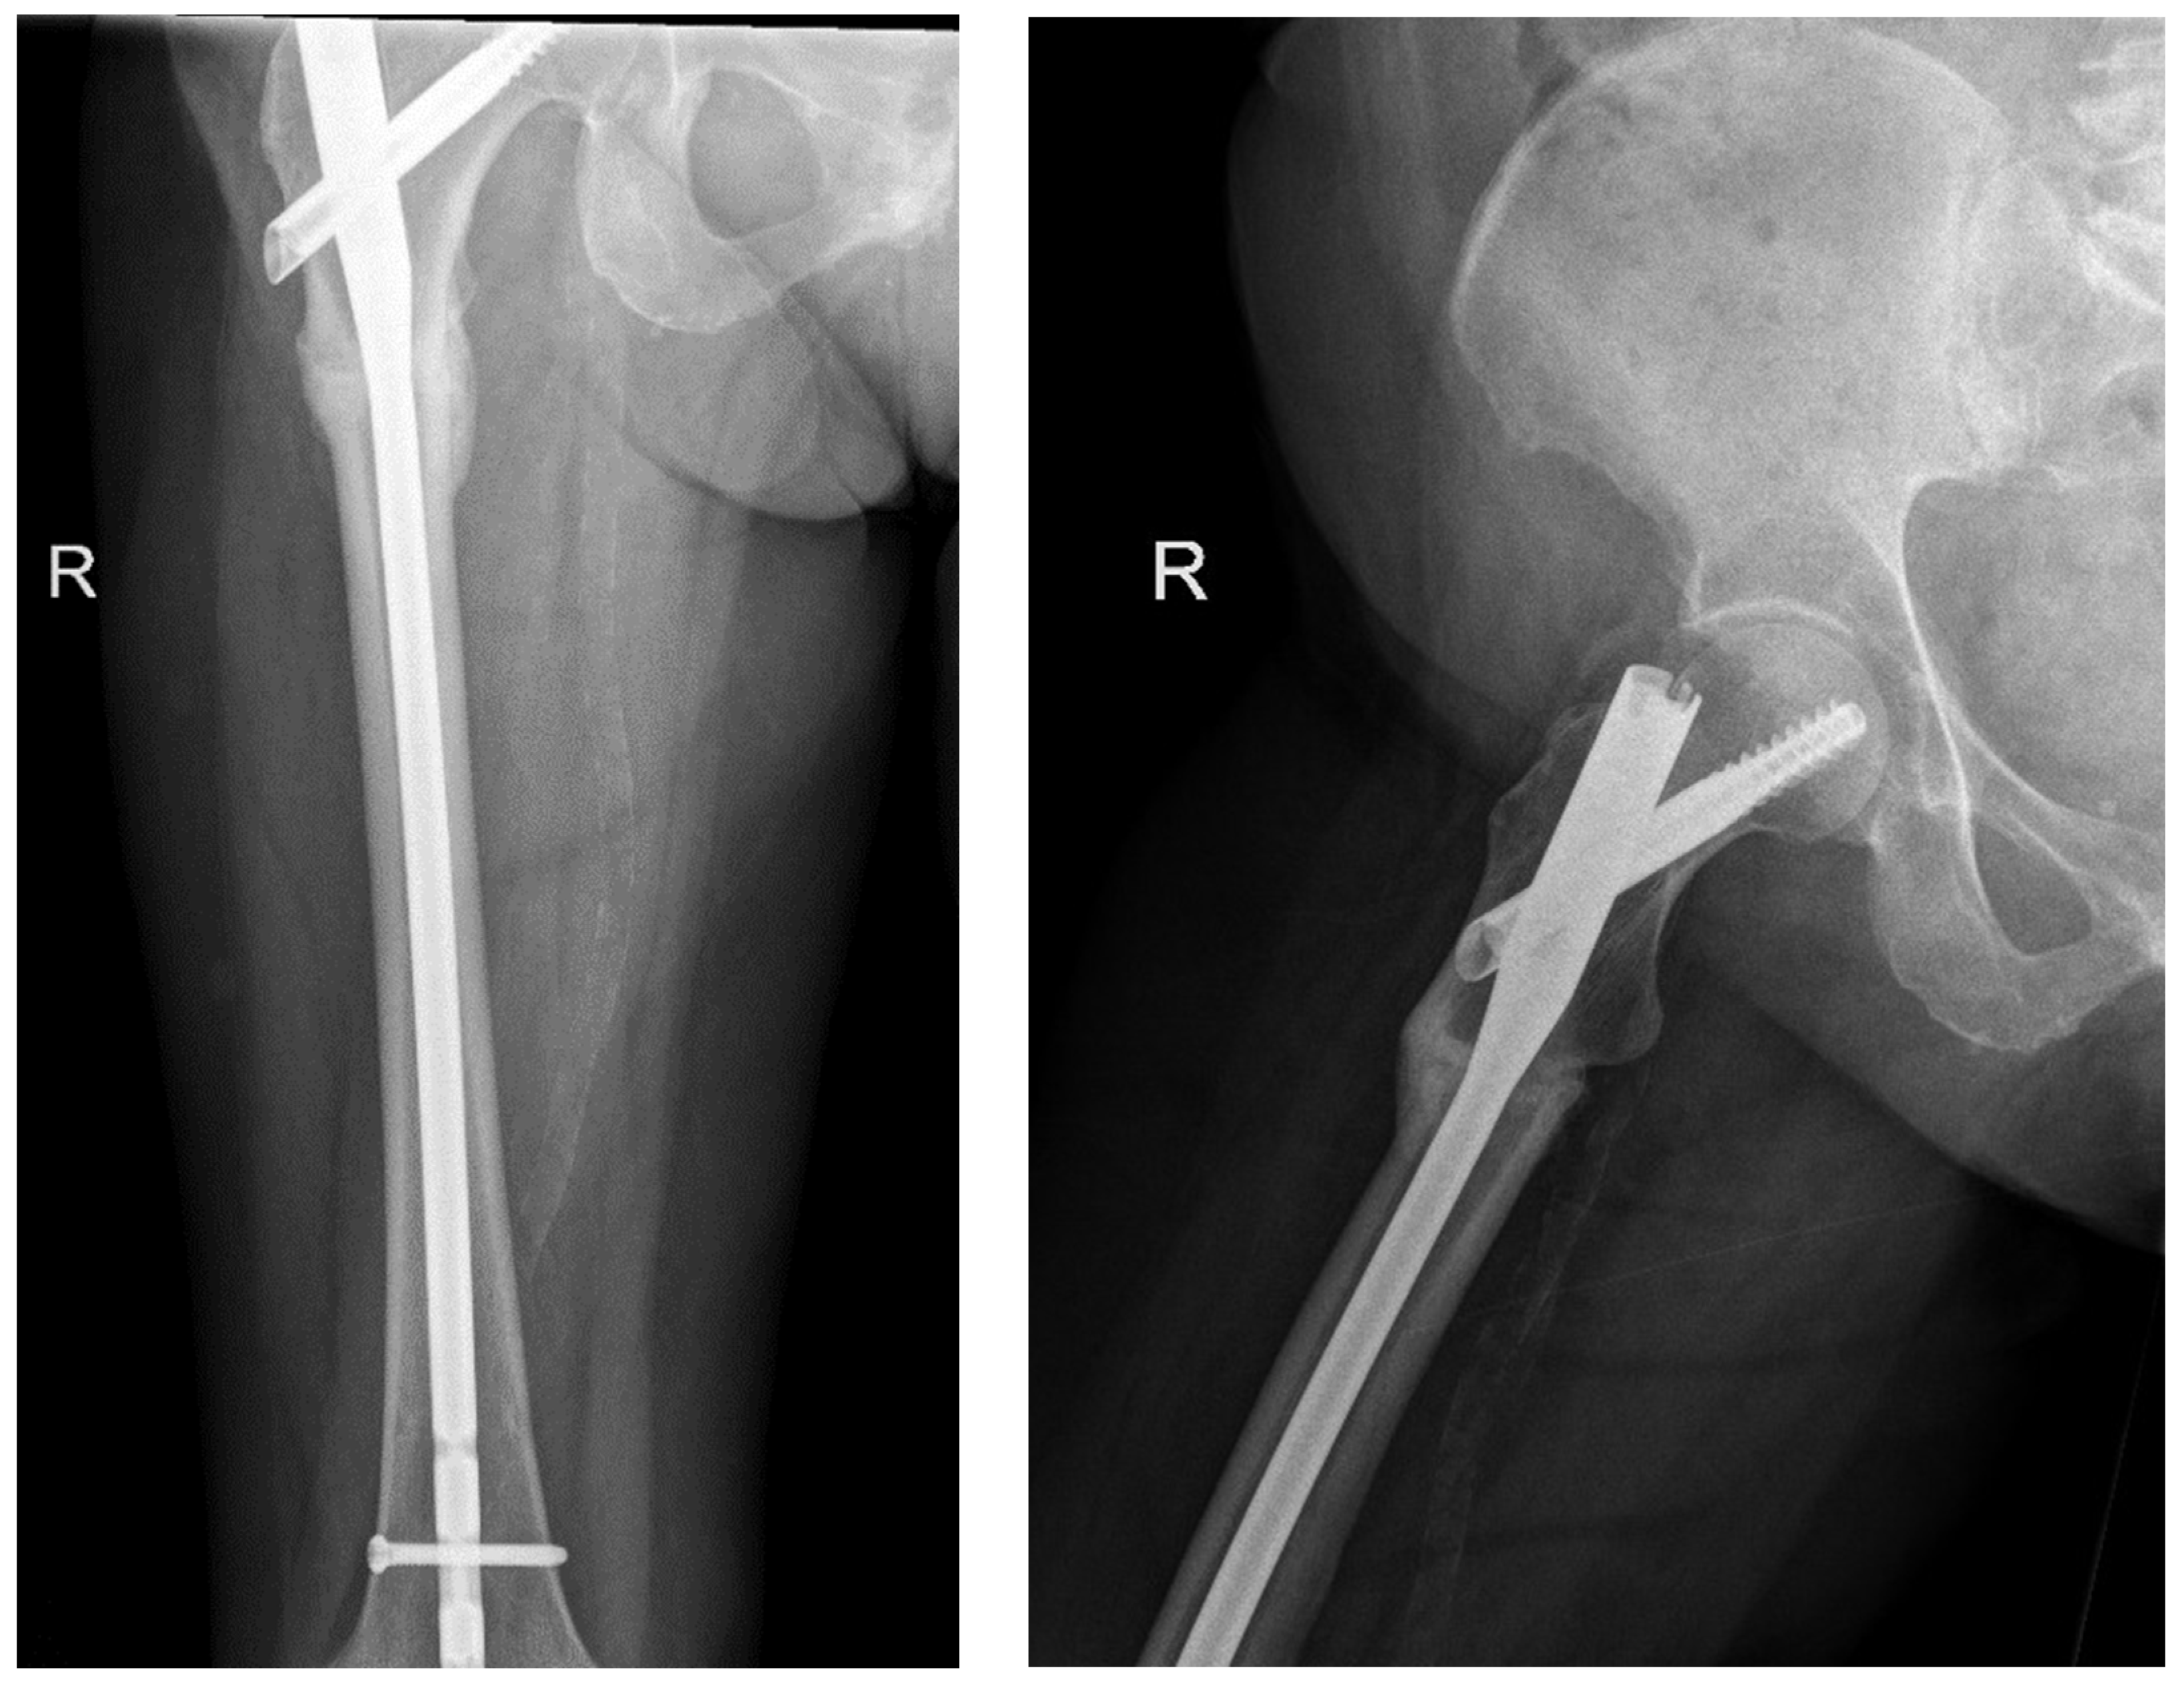

The following radiographs present the initial radiographs from the day of injury along with those obtained during the final OPD follow-up of the patient. The sequence presents radiographs demonstrating full radiological union (Scheme 1 and Scheme 2) and X-rays with no evidence of fracture healing at the final OPD follow-up (Scheme 3 and Scheme 4).

Scheme 3. X-ray of right femur AP view (left) and lateral view (right) of atypical subtrochanteric stress fracture—July 2022.

Jcm 14 02858 sch003

Scheme 4. X-ray of right femur AP view (left) and lateral view (right) of atypical subtrochanteric stress fracture—September 2024 (no features of healing).

Jcm 14 02858 sch004